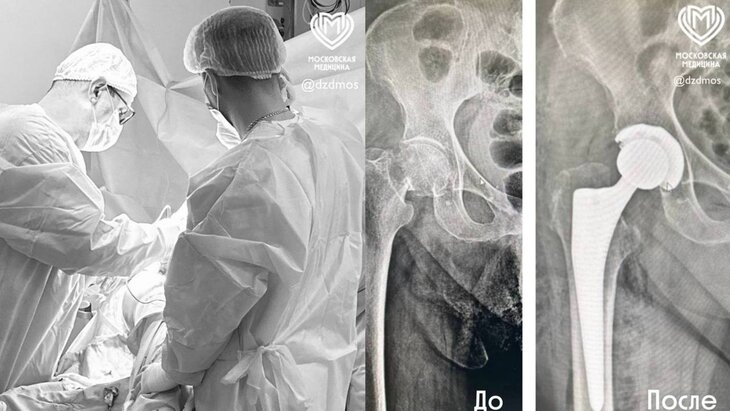

Фото: телеграм-канал "Московская медицина"

Врачи городской клинической больницы имени А. К. Ерамишанцева заменили тазобедренный сустав 103-летней пациентке. Об этом сообщила пресс-служба столичного департамента здравоохранения.

Женщину на скорой привезли в медучреждение после того, как она неудачно упала дома и сломала шейку бедра. В результате ей была сделана операция, в рамках которой врачи заменили пациентке тазобедренный сустав. Благодаря этому хирургическому вмешательству функция сустава была полностью восстановлена.

На следующий день после операции женщина смогла двигаться, а через четыре дня ее выписали с рекомендациями по реабилитации. Врачи отмечают, что после полного восстановления пациентка сможет ходить без опоры.

В свою очередь, заведующий травматолого-ортопедическим отделением больницы Ваагн Папоян назвал случай пенсионерки специфическим. Он указал, что с возрастом кости становятся менее плотными, более хрупкими и склонными к переломам. В связи с этим врачи уделили много внимания креплению эндопротеза, чтобы женщина смогла вернуться к привычной активности.